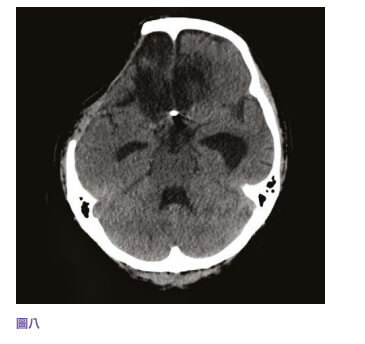

中风当时39岁的李先生三年前,39岁的李先生是位地盘工人,已婚育有一名幼子,为家庭经济支柱。 他身体一向健康,经常运动而且不烟不酒。 某日在工地里突然急剧头痛,继而晕倒在地。 工友立即召唤救护车将他送往附近的公立医院,送院时李先生还是半清醒。 电脑扫描显示他脑部有蜘蛛网膜下腔出血性中风(见图四),从造影可以看到一个约一至二毫米的动脉瘤在李先生大脑的前交通动脉血管之上(见图五)。 不幸的是,在医院观察的第二天早上,李先生突然深度昏迷,紧急电脑扫描显示动脉瘤第二次爆破,而且造成脑部严重积血、颅内压飙升,专科医生需要做紧急开颅手术去清除脑内血块,并将脑室引流以减低脑积水和颅内压(见图六),同时用钛金属夹将爆破的动脉瘤夹闭(见图七),防止它再次爆破。